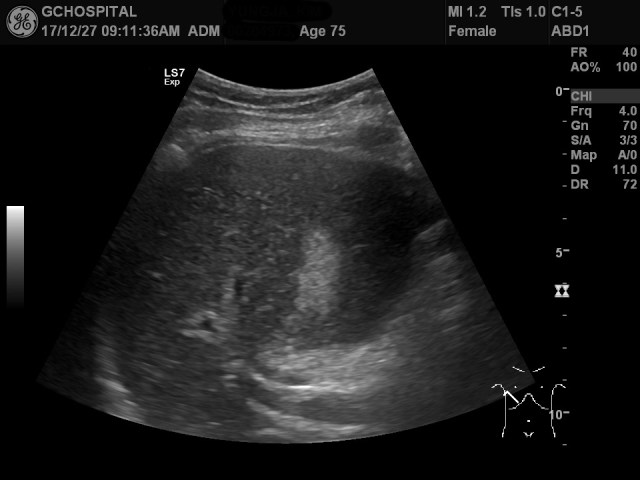

75세 남자환자로 우상복부 통증과 고열을 주소로 내원했습니다. 초음파상 위와 같이 쓸개 내에 결석이 보이고, 쓸개벽이 두꺼워져 있었으며, 전형적인 머피 사인이 보여 급성 담낭염으로 진단하고 내과에서 입원치료중이었습니다.

문제는 이 초음파를 시행하면서 심한 압통과 환자의 비협조로 인해 간의 지붕쪽을 확실하게 체크를 하지 못하고 넘어갔던 점입니다. 위 영상이 간의 지붕부위를 체크한 영상인데, 다시 보면 간실질이 또렷하게 보이지는 않았음에도 불구하고, 일단 주된 증상에 대한 진단이 내려졌기 때문에 방심하고 검사를 끝냈던 것 같습니다.